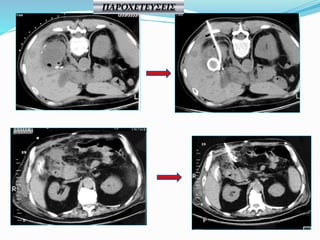

ΠΑΡΟΧΕΤΕΥΣΕΙΣ

ΚΑΘΕΤΗΡΕΣ 8-24 F